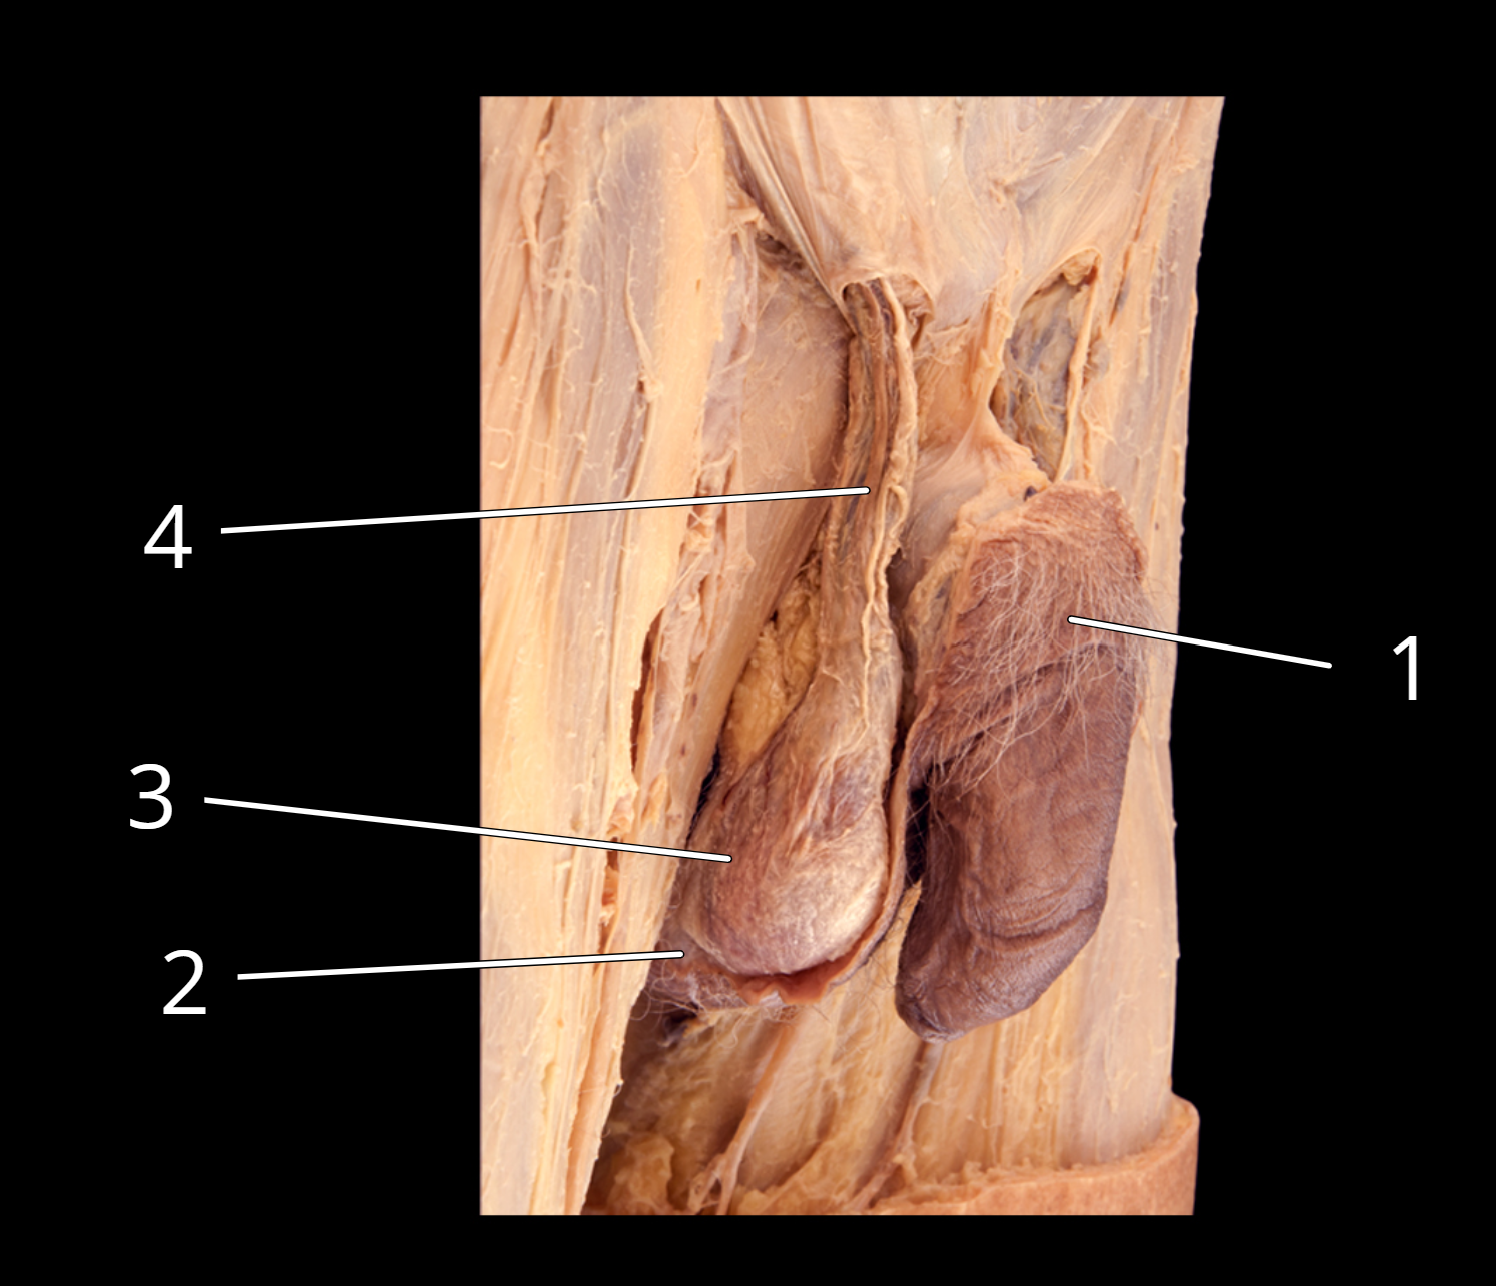

Penis and testis, lateral view

1. Penis

2. Scrotum, cut

3. Testis in external spermatic fascia

4. Spermatic cord